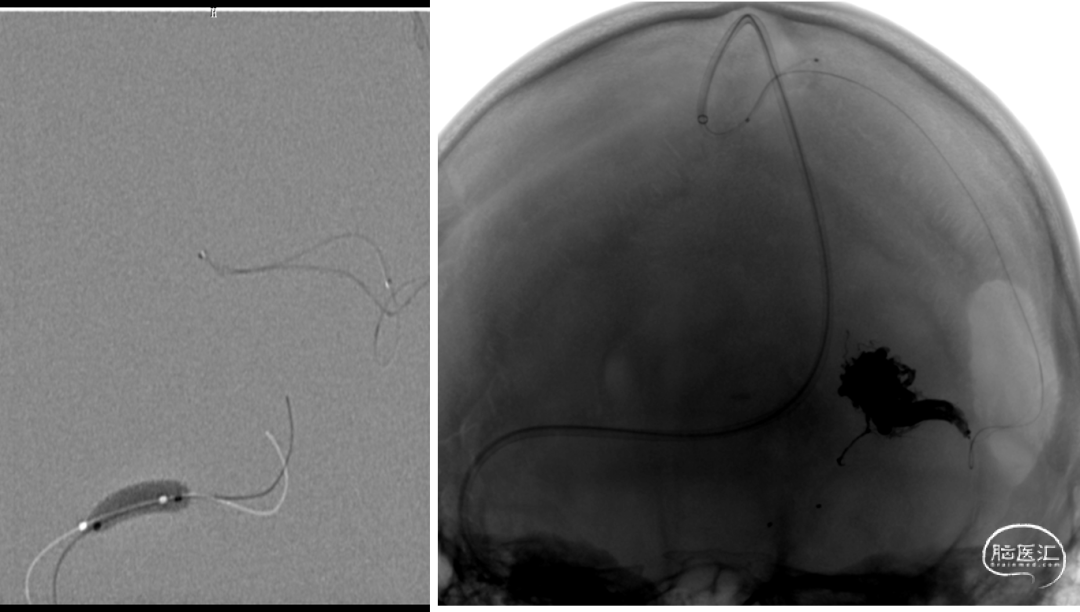

动静脉联合3d显示引流静脉与矢状窦关系;中天21微导管塑形(半圆)支撑下FATHOM-14导丝超选成功,考虑enchlon10长度不够,截断中管;FATHOM-14 3m交换enchelon10,但阻力大未能到位,中间管也未能到引流静脉入口;头羊作用下apollo3cm超选到位。

球囊保护静脉入路栓塞:注射onyx34约1ml,onyx18约1.5ml,总时长20min。

手术材料

•通路:

动脉:

6F鞘,8F导引导管,球囊微导管

静脉:

8F鞘,8F导引导管,颅内支撑导管TGC070-06-125(中间导管),Echelon10微导管,Apllo微导管

• 微导丝:

泥鳅导丝,Synchro-10 200cm,FATHOM-14 200cm,FATHOM-14 300cm, PILOT200 190cm

•球囊:

HyperGlide 3*10mm

•栓塞材料:

Onyx18 、Onyx34